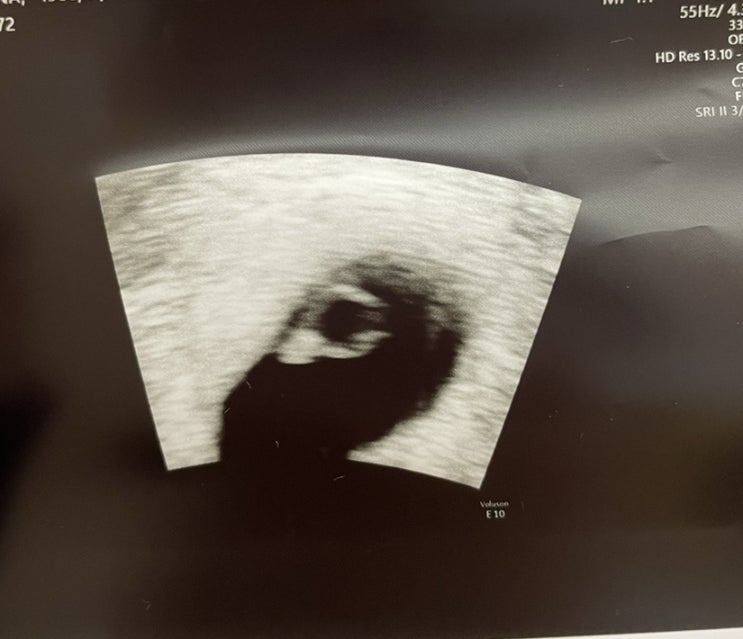

둘째 출산을 앞두고

이제 애플이 출산 예정일이 68일 남았다. 두달여가 남았는데, 둘째는 좀 일찍 나온다고 하기도 하던데.. 어...